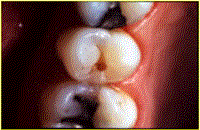

También se ha podido reemplazar las amalgamas. Este tipo de material logra una ecxelente estética y función cuando la cavidad de caries es pequeña.

Si las caries son grandes puede ser reemplazada por incrustaciones de resina termopolimerizadas o de cerámica preformada, como muestra la secuencia.Y no hay duda que el avance en este campo continuará mejorando los materiales y bajando los costos de dichas prestaciones, para beneficio de nuestros pacientes y el propio.